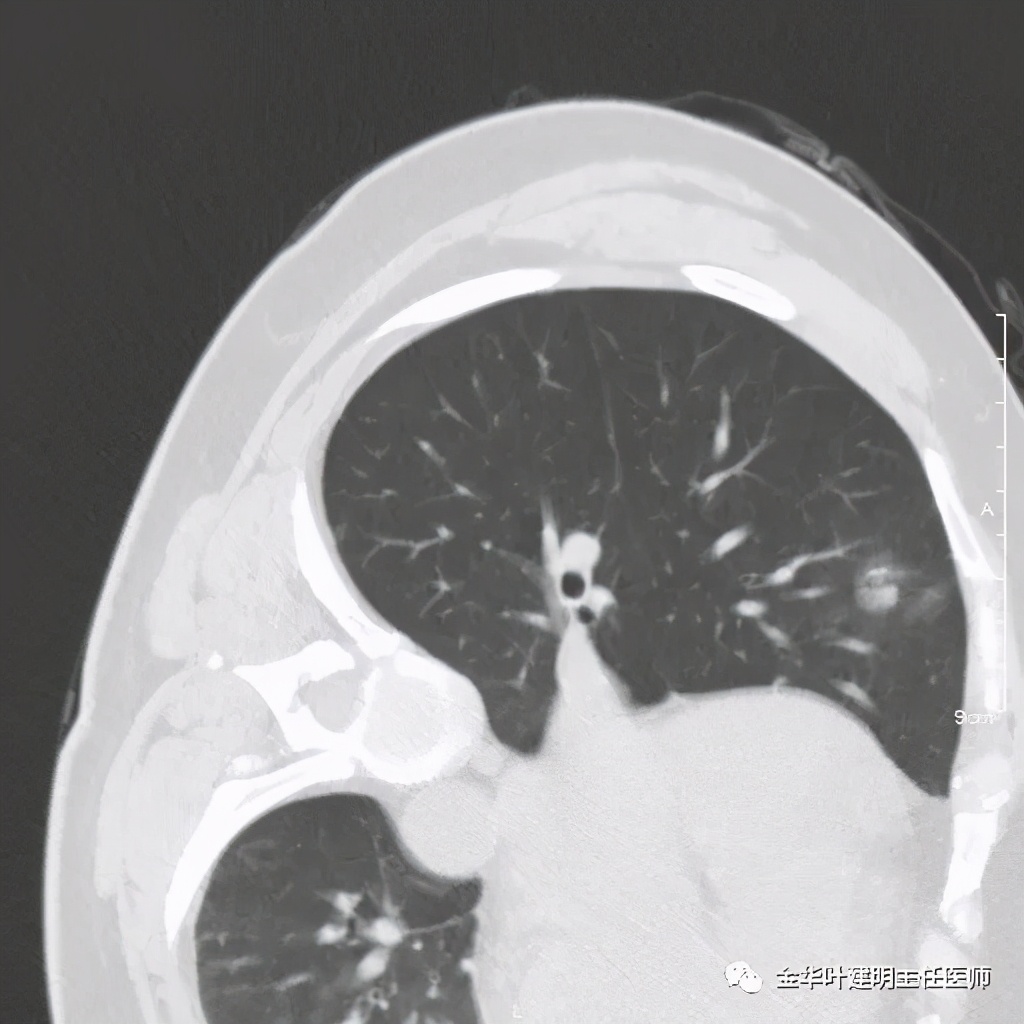

五、浸润性腺癌之粘液腺癌:

影像特征:这个病例是我在术前仅凭影像就判断其为粘液腺癌,术后确诊的。粘液腺癌表现为 实性乏收缩力、密度较均匀 的实性结节。病灶的边界一般非常清楚,没有毛刺、磨玻璃、卫星灶等,但又乏收缩力,像本例紧贴胸膜也不会有牵拉凹陷;同时病灶的密度又比较均匀(粘液成份)。良性肿瘤密度要更高些、慢性炎没有这么光整的边界,也容易有瘢痕收缩方面的影像表现、其他实性的腺癌则要有收缩力、腺泡型虽然也缺乏收缩力,但密度要不均匀些。